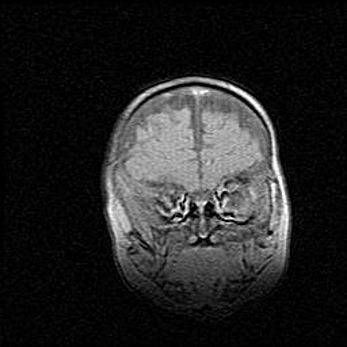

Подострая гематома правой гемисферы мозжечка.

Наружная гидроцефалия.

Возраст: 15 дней

Вес: 3100 г

Пол: женский

Окружность головы: 37 см

Срок гестации: 35-36 недель

При открытой наружной форме гидроцефалии у новорожденных расширяются и переполняются субарахноидные пространства.

Кровоизлияния в мозжечок имеют две клинико-анатомические формы: полушарные гематомы и кровоизлияния в червь.

К появлению этой патологии может привести: повреждения головного мозга, возникающие в результате асфиксии и гипоксии плода при беременности, или травмы во время родов. Редко гематома мозжечка может быть результатом первичной коагулопатии и сосудистой мальформации, диссеминированном внутрисосудистом свертывании, изоиммунной тромбоцитопении.